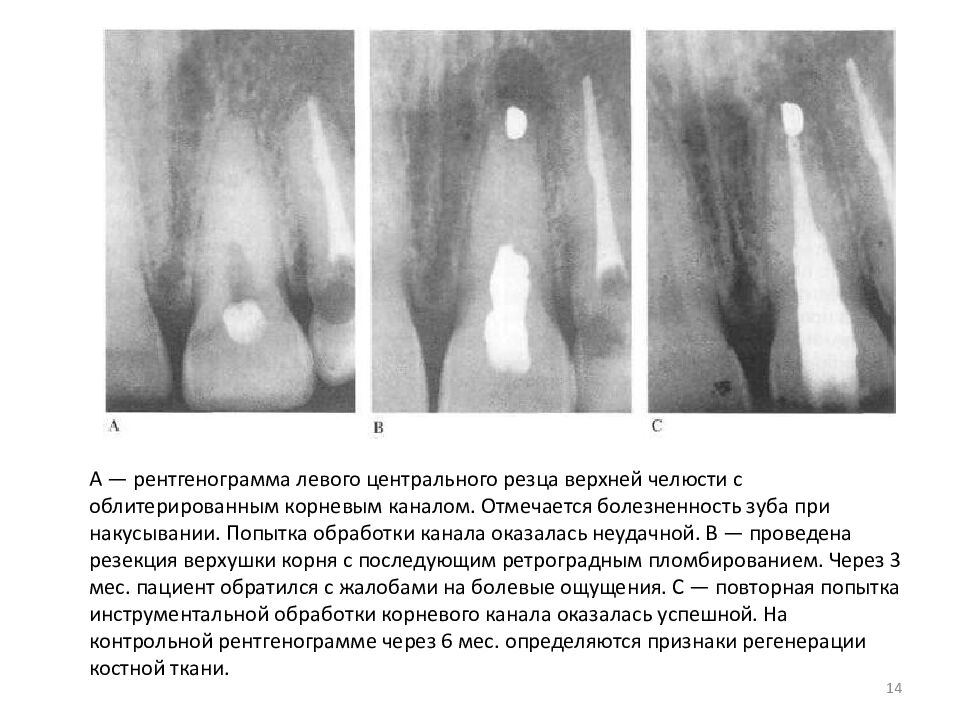

А — рентгенограмма левого центрального резца верхней челюсти с облитерированным корневым каналом. Отмечается болезненность зуба при накусывании. Попытка обработки канала оказалась неудачной. В — проведена резекция верхушки корня с последующим ретроградным пломбированием. Через 3 мес. пациент обратился с жалобами на болевые ощущения. С — повторная попытка инструментальной обработки корневого канала оказалась успешной. На контрольной рентгенограмме через 6 мес. определяются признаки регенерации костной ткани. 14